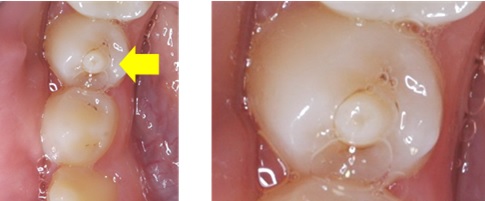

結節突起的構造一樣有牙釉質及牙本質,底下也有牙髓神經延伸至此,突起的形態使得咬合力集中在此處,

容易發生過度磨耗甚至整個牙阜斷裂

,導致底下牙髓暴露而感染、壞死。

最好能在牙齒剛萌發(約9歲~11歲) 以樹脂將整個中央牙阜覆蓋住,避免咬合磨耗,

中央牙阜周圍也需填補起來,做預防性補強,避免過强咬合力造成中央牙阜斷裂。

若會咬到對咬牙,須將對咬牙的咬合干擾磨除,並塗上氟漆強化牙釉質。

中央牙阜有時也容易造成牙髓壞死,則需進一步作根管治療。